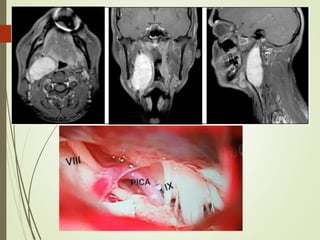

CRANIECTOMÍA SUBOCCIPITAL

La rizotomía percutáneadebe realizarse con equipo de arco en "C" introduciendo la aguja aproximadamente a 2,5 cm de la comisura labial y con un ángulo de 14 grados en sentido caudal a la proyección del foramen oval, siguiendo misma dirección sagital utilizada para la rizotomía trigeminal. Ubicado el foramen yugular se produce la estimulación correspondiente la cual ocasiona tos y contracción del esternocleidomastoideo. Posteriormente se produce la lesión por radiofrecuencia. Las complicaciones relacionadas a la rizotomía percutánea y a la sección intra o extracraneal del glosofaríngeo incluyen: disfagia permanente, ronquera, parálisis de las cuerdas vocales, abolición del reflejo nauseoso. Por lo cual la descompresión microvascular representa una opción terapéutica válida ya que evita la presentación de estas complicaciones y al mismo tiempo provee una solución permanente a la neuralgia